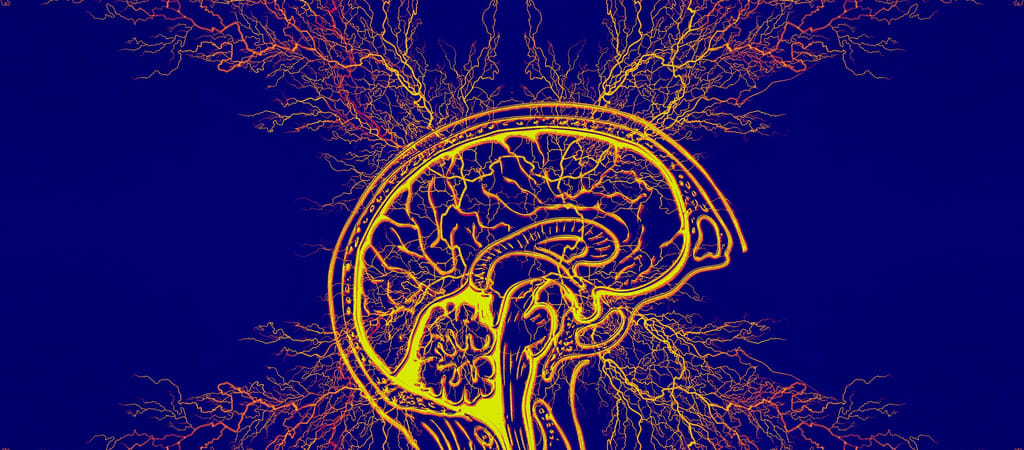

A 21 éves, nem megnevezett nő epilepsziában szenvedett, az agyának motoros központjánál egy lézió (térfoglaló folyamat) volt. Az interfész segítségével a NeuroXess rögzíteni és elemezni tudta az agykérgi térpotenciálokat (ECoG) a páciens agyi jeleinek magas gamma-sávjából. Ehhez egy 256-csatornás, nagyteljesítményű, flexibilis BCI-t ültettek be az agyába.

A szakemberek a beavatkozást követően néhány perccel már pontosan fel tudták térképezni a páciens agyfunkcióit. A szerzett, 70 és 150 hertz közötti magasgamma-sávos adatokat egy neurális hálózati modell betanítására használták fel, ami valós időben tudja dekódolni az agyi jeleket, mindössze 60 milliszekundumos késleltetéssel – részletezi az Interesting Engineering.